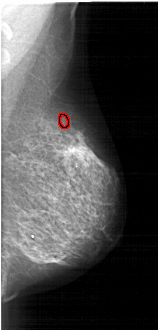

A_1784_1.RIGHT_CC

RIGHT_CC LINES 5026 PIXELS_PER_LINE 2581 BITS_PER_PIXEL 12 RESOLUTION 43.5 OVERLAY

FILE: A_1784_1.RIGHT_CC.OVERLAY

TOTAL_ABNORMALITIES 1

ABNORMALITY 1

LESION_TYPE CALCIFICATION TYPE PLEOMORPHIC DISTRIBUTION CLUSTERED

ASSESSMENT 4

SUBTLETY 2

PATHOLOGY BENIGN

TOTAL_OUTLINES 1

BOUNDARY